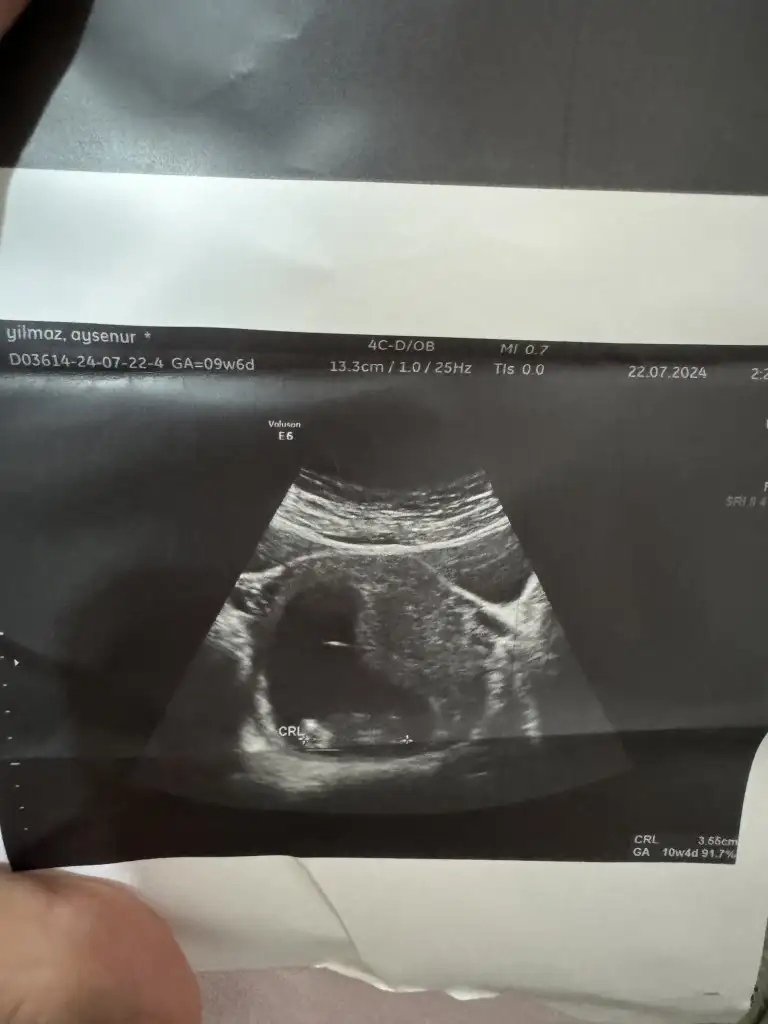

Bende çok merak ettim bak şimdi 3 gebeliğin bu 2 ohlum var bakalım bu ne olacak hayırlısıyla 10 haftalik fotoğrafı karından ultrason

• 1000030880.webp

1000030880.webp

15,3 KB · Görüntüleme: 65